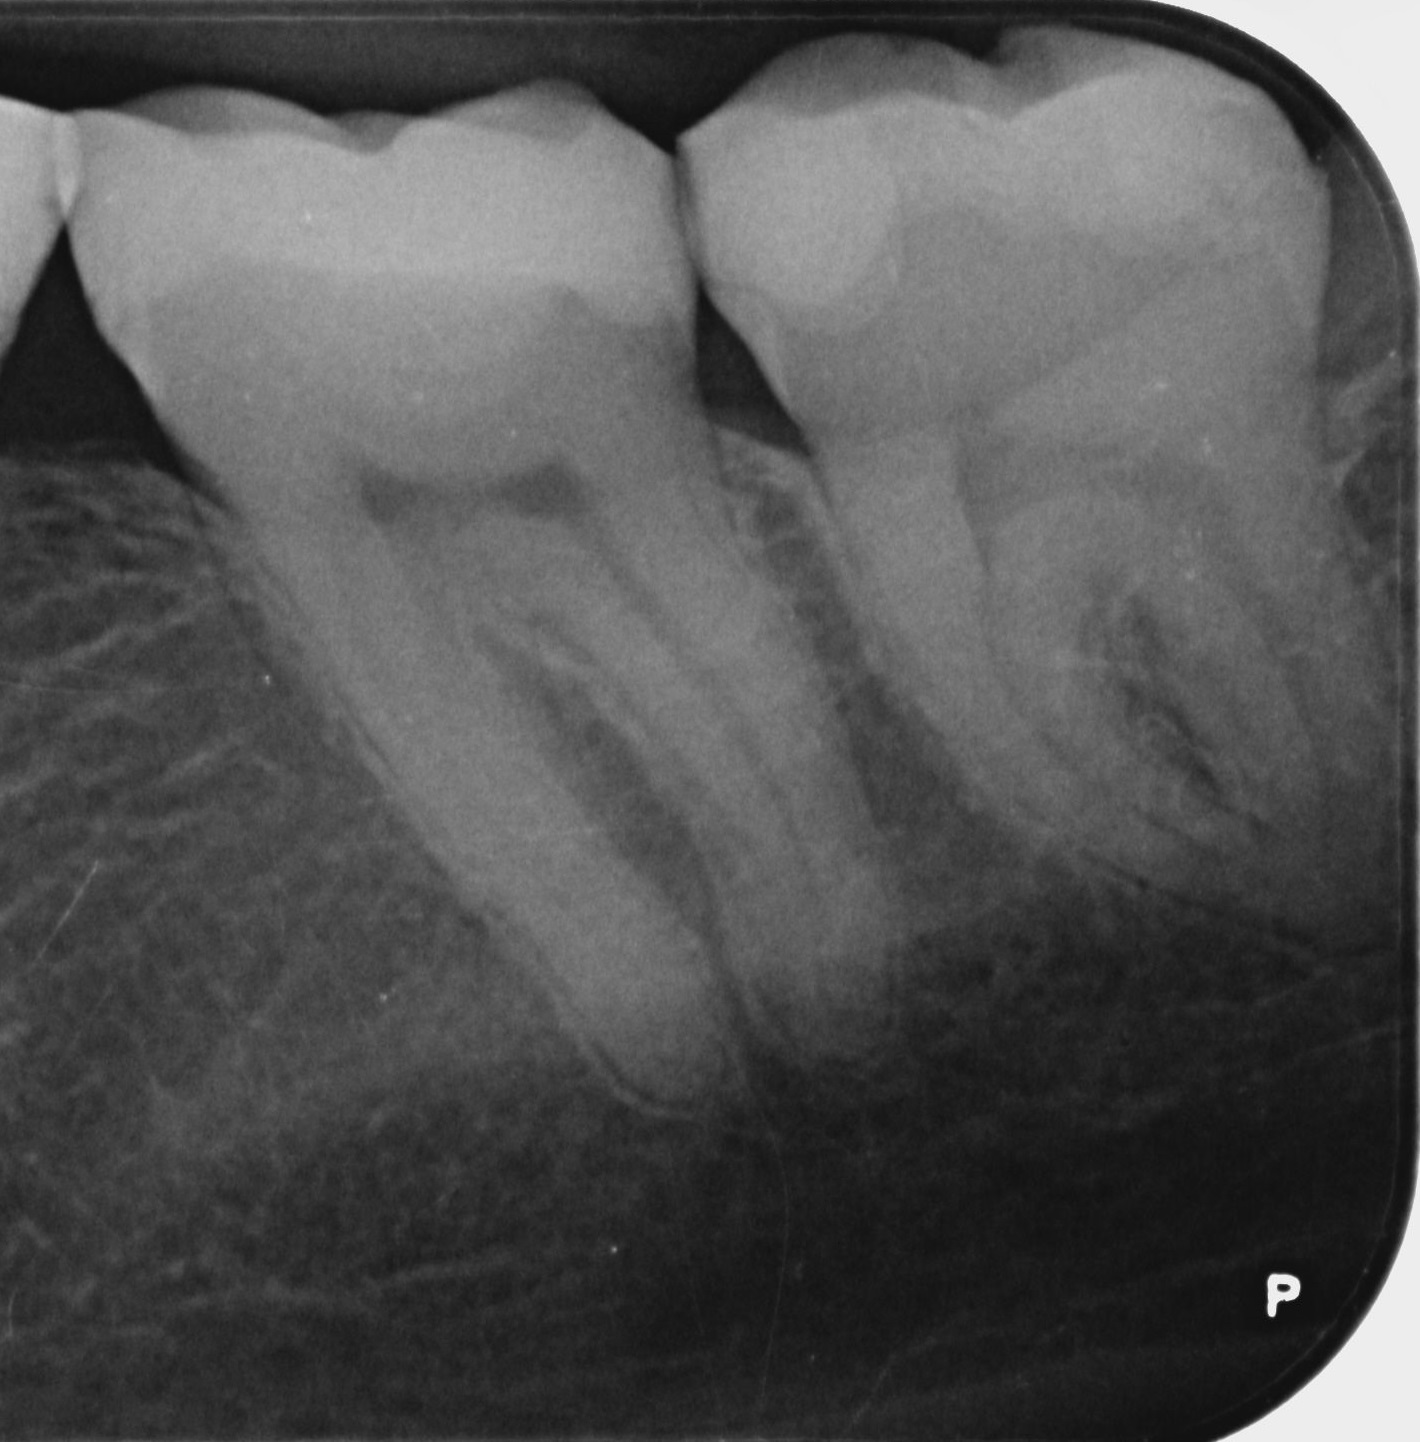

Mijn vraag aan jullie is dan, zien jullie iets op dit foto ?

Zijn de vullingen zo diep om pulpitis te kunnen veroorzaken ? Kan een kies 2 jaar lang pulpitis hebben zonder af te sterven ? Of lijkt dit eerder uitgesloten gezien het verloop en de beelden ?

Die vullingen, zijn die "diep genoeg" om te kunnen spreken over oorzaak van necrose ?